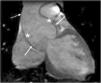

A principal manifestação cardiovascular da SM consiste na dilatação da raiz da aorta e da aorta ascendente proximal com apagamento da junção sino‐tubular, presente em 80% dos doentes, e conduzindo eventualmente à disseção da aorta, principal causa de morte prematura nestes doentes (Figuras 5 e 6) 3,12,41,49–51. A aorta ascendente é, neste contexto, a porção da árvore arterial mais afetada pelo desenvolvimento aneurismático devido ao seu maior conteúdo em fibras elásticas e à exposição ao stress hemodinâmico repetitivo da ejeção do ventrículo esquerdo2,50,52,53.

O estudo cardiovascular é efetuado habitualmente recorrendo a um ecocardiograma transtorácico, validando‐se o maior valor do diâmetro da raiz da aorta registado ao nível do seio de Valsalva, de entre pelo menos três imagens transtorácicas. O valor medido da raiz da aorta deve ser corrigido de acordo com a idade e a área de superfície corporal e interpretado de acordo com o Z‐score. Roman et al. criaram um nomograma para definição do diâmetro da raiz da aorta em relação com a área de superfície corporal e a idade6,70,71. Se o ecocardiograma transtorácico não permitir uma visualização precisa da aorta proximal, deve realizar‐se ecocardiograma transesofágico, tomografia computadorizada ou ressonância magnética, que também são indicados para o estudo da aorta distal. O uso do mesmo nomograma está indicado para se determinar o valor correto do diâmetro da raiz da aorta6. A ecocardiografia é também importante para a avaliação das alterações morfológicas e funcionais das válvulas mitral e tricúspide.